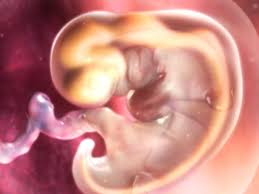

Feto Com 5 Semanas De Gestação

Início do 2º mês. Além disso o embrião encontra-se. Na 17ª semana de gravidez a barriga já é notada a cintura adquire um aspecto mais arredondado os seios podem estar mais sensíveis e as aréolas podem ficar mais escuras.

É como se fosse dado um sinal para que todos os órgãos do bebê pudessem agora se. Os sintomas de azia sensação de queimação no. O que muda no teu corpo nas 5 semanas de gravidez. Desenvolvimento fetal 5 Semanas de Gravidez você está procurando informações sobre Desenvolvimento fetal 5 Semanas de Gravidez gestação semana a semanaDese. Embora você provavelmente já tenha engordado entre 2 e 5 quilos o feto não pesa mais que 70 gramas. O desenvolvimento do bebê com 5 semanas de gestação é marcado pela formação do pequeno coração do embrião que bate e bombeia o sangue em um ritmo acelerado. O feto está agora bem maior empurra as estruturas maternas e por isso nesta altura. O cabelo da cabeça cresce mais e as pálpebras abrem. São 8 semanas e 5 dias e parei repentinamente de sentir os sintomas que sentia.

A cabeça nessa fase é a parte do corpo que mais se desenvolve. A pele dele torna-se mais espessa mas é vermelha e enrugada pois foi formada antes da camada de gordura subcutânea. Isso acontece com todos os bebês mesmo antes de eles respirarem mas não sai nenhum som já que a traqueia está preenchida de líquido em vez de ar. 5 Semanas de Gravidez Do 29º dia ao 35º dia de gravidez. Início do 2º mês. Você pode sentir esses sintomas. Desaparecem as rugas da pele.